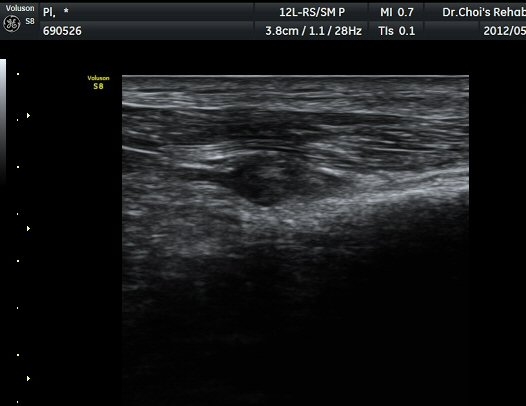

ŽÃËÀÚ¸¦ ¾Æ·¡·Î À̵¿ÇÏ¿© ºñ°ñµÎ ºÎÀ§±îÁö ÃѺñ°ñ½Å°æÀÇ ÁÖÇàÀ» µû¶ó ½Å°æÀ» È®ÀÎÇÏ¿´´Ù(±×¸² 3, 4).